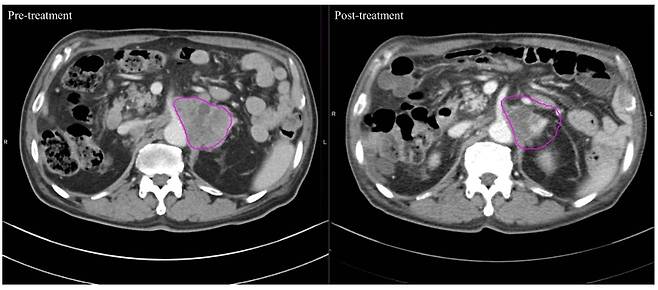

고주파 온열치료 전(왼쪽)보다 치료 후(오른쪽)암 병변 부위가 줄어든 사진. /사진=장홍석 교수 연구팀 논문 발췌몸속 온도를 '암이 싫어하는 온도(40~43도)까지' 끌어올려 암을 죽이는 '고주파 온열치료'는 새로운 암 치료법 중 하나로 꼽힌다. 이런 가운데 고주파 온열치료를 받은 암 환자들이 방사선 치료받은 환자들보다 암 덩어리가 더 빠르고 효과적으로 줄어든 사실이 국내 '빅5' 병원인 서울성모병원의 연구 결과로 나와 눈길을 끈다.

24일 국제바이러스연구연합(IVRA) 조직위원회에 따르면 장홍석 서울성모병원 방사선종양학과 교수 연구팀은 2019년 1월부터 2022년 3월 말까지 고온 온열치료 환자 20명과 방사선 단독 치료 환자 20명 등 전이성 복부 림프절 치료 환자 총 40명을 대상으로 컴퓨터 단층촬영(CT) 이미지를 모았다. 그리고서 치료 전후 종양 괴사의 변화를 관찰하는 지표(하운스필드 단위·Hounsfield Unit·HU)값의 변화를 비교해 치료 효과를 평가했다.

그랬더니 고온 온열치료 그룹은 치료 후 HU 값이 평균 9.05%(-8.47HU) 낮아진 58.95로 나타났다. 반면 기존의 방사선 치료 그룹은 0.57%만 줄어든(-0.41HU) 71.42였다. 이번 연구 결과는 최근 국제학술지 '플러스 원(PLOS ONE)'에 발표됐다.